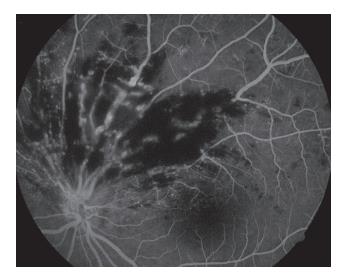

20230106113317_1967.jpg

图9 左眼眼底荧光血管造影见颞上方网膜可见新生异常血管网(发病103 d)

Figure 9 Fluorescein fundus angiography of the left eye showed abnormal neovascularization network of the supratemporal retina (oneset of 103 d)